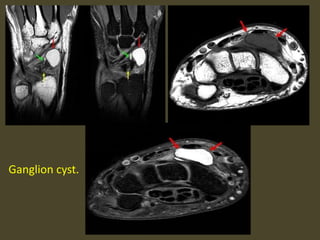

Ganglion cyst.